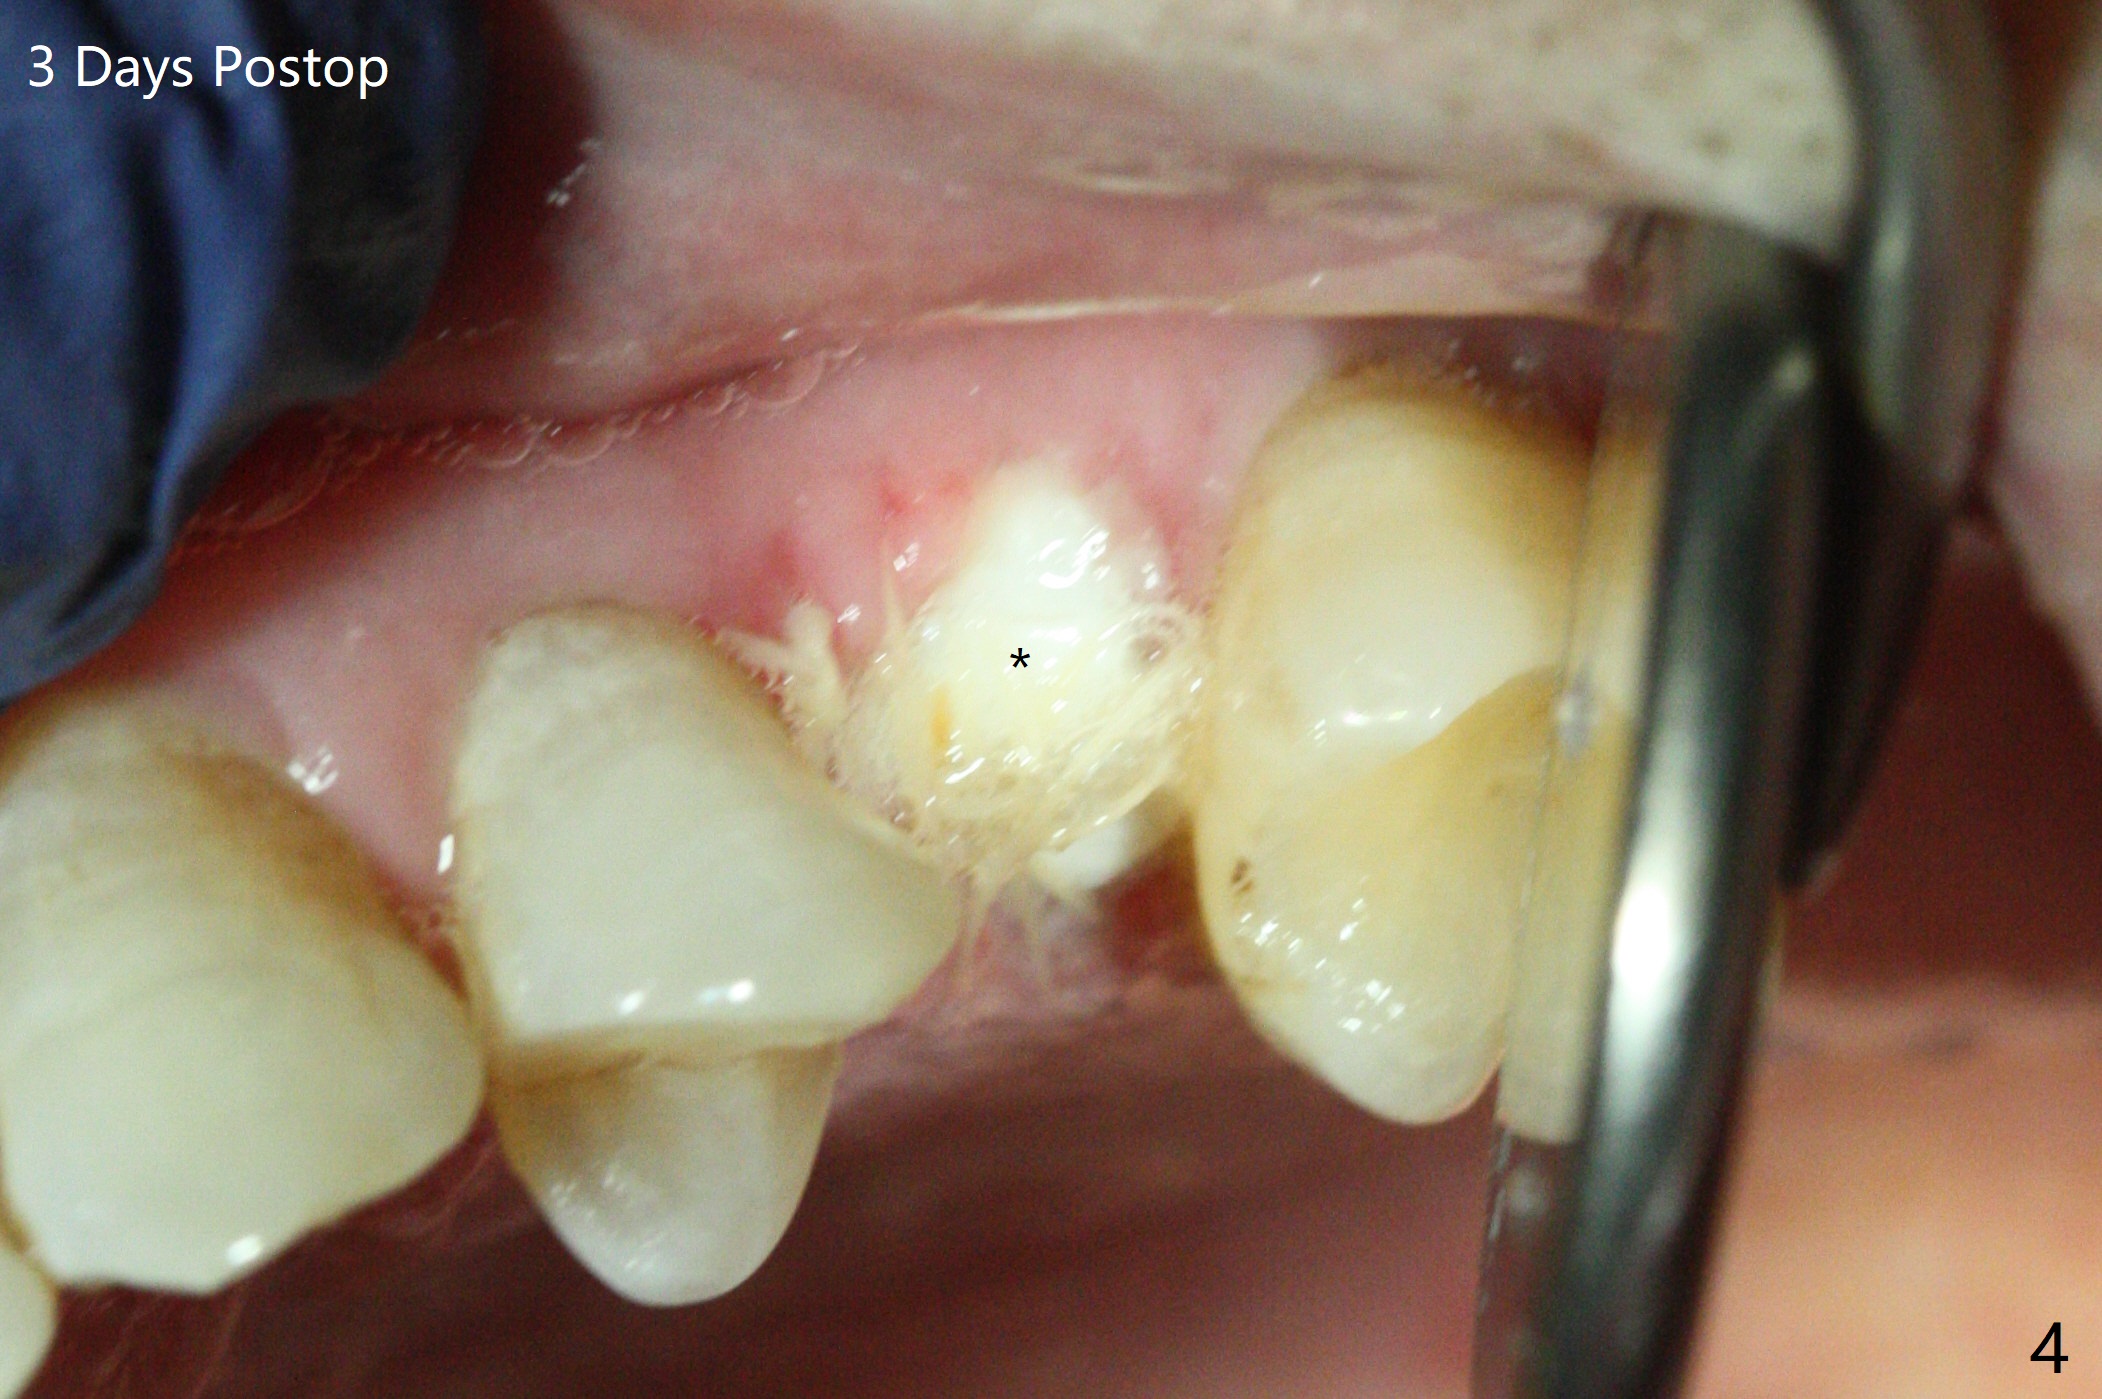

A 65-year-old man cracks 3 teeth in ~2 years (Fig.1,2 (#4,13,15)). The tooth #4 is symptomatic after RCT (Fig.1); it appears that the buccal canal is incompletely filled (data not shown). In fact an exam 1 month later shows that the symptomatic tooth is #2 (crack), while #4 is salvageable (Fig.8). The tooth #13 has palatal subgingival fracture with severe pain (Fig.2 with palatal defect). In fact the title of this case is incorrect). After extraction, allograft is placed (Fig.3 *) with 6-month membrane. In fact the bone graft is not packed into the apex of the socket; a condenser should have been used. The patient returns 3 days postop before leaving abroad. The 6-month membrane remains in place (Fig.4), while the ridge at #15 is minimally atrophic (Fig.5). The coronal lamina dura becomes indistinct 5 months postop (Fig.6). The bone graft remains in the socket. The distoapical portion of a 4x11.5 mm implant may be in the sinus (Fig.7).